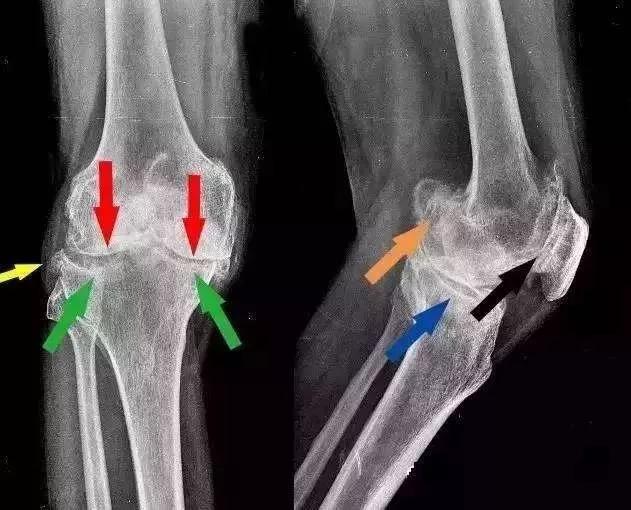

此时人体还面临一个严峻的情况——骨质增生。

骨质增生是人体衰老的正常退化现象,一般不会引起症状。只有增生的骨刺伤到周围策划后才会出现不适。

膝关节长期承受较大压力,软骨磨损严重,增生的骨刺很容易深入到周围策划,引发一系列病变。

随着病情发展,出现关节积液、关节囊肿胀。

进行剧烈运动后,膝关节会出现急性炎症表现:疼痛、发热、红肿,休息或者涂抹消炎药膏才能缓解。